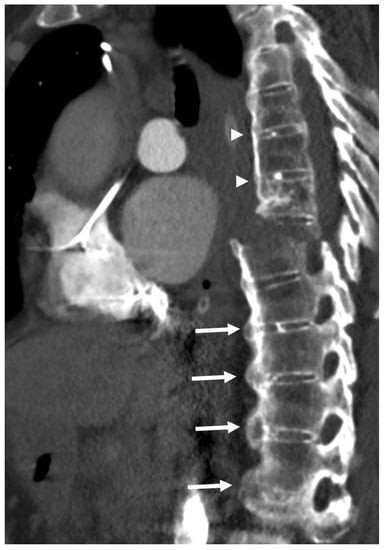

An ankylosed spine, such as that observed in DISH, is rigid and, as a result, is susceptible to injury, even from low-energy trauma. DISH is associated with a prevalence of thoracolumbar vertebral fractures of 4–18%, of which multilevel fractures are reported in about 8% [56,57]. These fractures are frequently extension-type fractures and are associated with a greater instability risk for spinal cord injury of up to 58% and a higher rate of complications (Figure 6) [58,59,60]. Fractures in DISH pass through the vertebral body, which is the most exposed and weakest point in the ankylosed spine [61]. Detection of vertebral fractures on radiographs of the spine of DISH subjects is challenging; thus, it has been suggested that whole-spine CT be performed in emergency response units in order to prevent negative consequences in DISH subjects, even after minor trauma [9,62].

Figure 6.

Sagittal CT reconstruction of the thoracic spine of a 78-year-old patient with thoracic DISH after low-energy trauma, showing an unstable extension-type fracture of the mid-thoracic spine. In the given slice, there are two vertically oriented bony bridges in the upper thoracic spine (arrowheads) that may lead to the misconception that this is a patient with ankylosing spondylitis; however, there are clearly many flowing osteophytes compatible with DISH in the lower part of the thoracic spine (arrows).